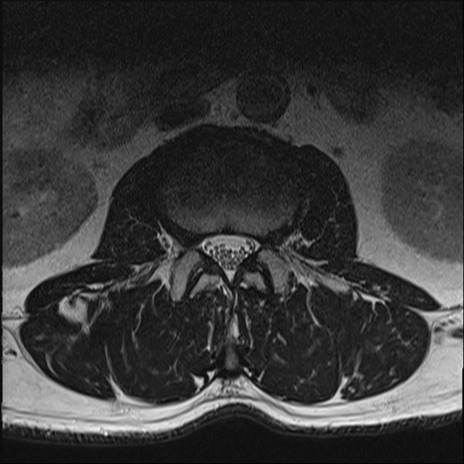

【整形】TIPS症例2 腰椎MRI T2WI(横断像)

【症例】70歳代男性

【主訴】左下肢痛

【現病歴】2週間前くらいから腰痛、左下肢痛あり。左臀部から大腿、下腿外側のしびれが常時ある。歩行とともに同部位の痛みあり。

【身体所見】Lasegue70-/60+、Bragard-/±、PTR ±/±、ATR -/-、IP 5/5、TA 5/4、TS 5/5、EHL 右第1足趾なし/3、FHL 5/5、hypersthesia(-)、足背動脈触知良好

異常所見と診断は?